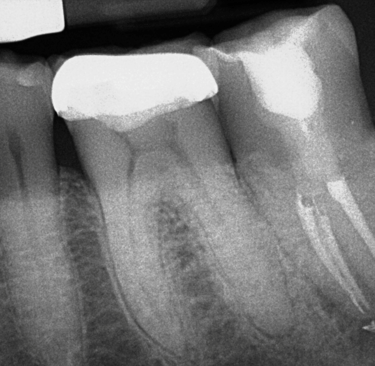

Thorough diagnostic testing and x-ray (radiographic) imaging will be completed to ensure an endodontic problem exists and if it’s the tooth with previous root canal treatment. Additionally, Cone Beam CT 3D imaging will be required to help identify the cause of failure, and to give exact and proper measurements needed for the procedure. Your medically history will also be thoroughly reviewed. The prognosis and description of intentional replantation will then be explained to you.

Treatment Completed by Dr. Battista